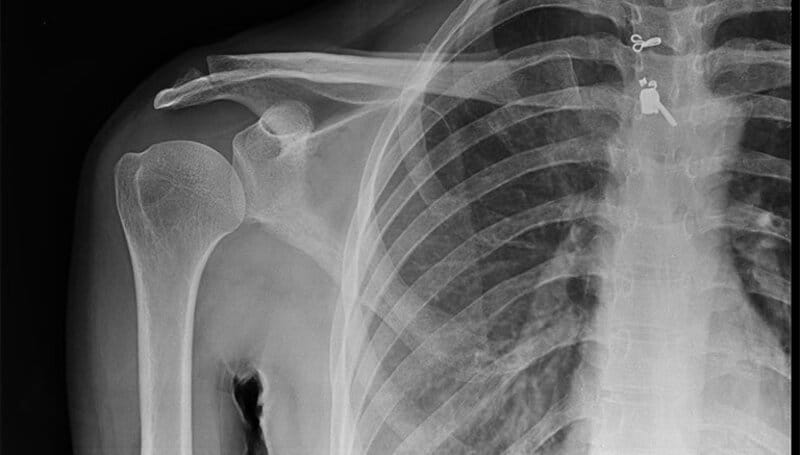

Chụp X-quang: Giúp phát hiện hẹp khe khớp, gai xương, mất lớp sụn khớp.

MRI hoặc CT scan: Đánh giá chi tiết hơn về mô mềm, cơ, dây chằng, bao khớp.